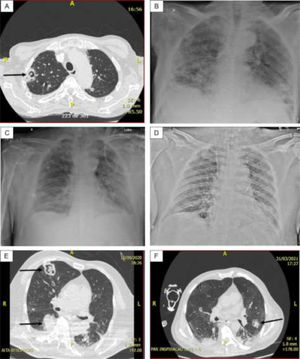

The most common radiographic finding in the 15 patients, generally attributed to SARS-CoV-2 infection, was bilateral interstitial pulmonary infiltrate associated with consolidations and areas of ground-glass opacity. Cavitations (n = 4) and/or pulmonary nodules with a diameter ≥ 1.0 cm (n = 5) were observed in cases 1, 2 (probable CAPA), 6, 7, and 8 (presumed CAPA) and considered suggestive of fungal infection (associated with pulmonary tuberculosis in case 8) (Fig. 1).

(A) Case 1 – Thorax CT: Cavitary lesion (arrow) and numerous nodules in both lungs; (B) Case 1 – Thorax radiography: Diffuse consolidations, ground glass areas and nodules in both lungs. (C) Case 3 – Thorax radiography: Diffuse interstitial opacities and consolidations, some of that resembling nodules; (D) Case 5 – Thorax radiography: Bilateral and diffuse interstitial opacities containing micronodules and condensation in the lower lobe of left lung; (E) Case 6 – Thorax CT: Diffuse interstitial opacities, cavitary lesion with inner amorphous mass (large arrow), macronodule (thin arrow), and condensation in the right lung; (F) Case 7 – Thorax CT: ground glass opacities, macronodule (arrow) and peripheral consolidations in both lungs.